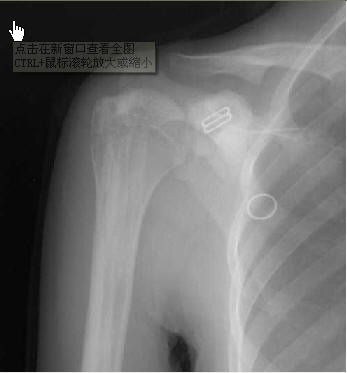

【原创】蜡油骨病1例 典型

学学,很少见的病例,前段时间,我们见到了.

病理:主要为骨内外膜增生,呈不规则硬化,骨干上新生骨堆积,可致轮廓变形,病变部位的造骨细胞活动增加及破骨细胞运动减少,故出现新骨形成。镜下可见病骨的哈氏管扭曲、变形,骨板层排列密集紊乱,骨小梁和骨髓腔可被纤维组织所代替。

蜡油样骨病常见的主诉:为局部疼痛和肢体活动受限,表现程度不同,休息时症状减轻或消失,活动时加剧。如涉及血管和神经,可出现神经痛、瘀血及水肿,严重时可致麻痹,关节附近增厚或周围软组织增厚引起运动障碍及畸形。局部触诊骨表现高低不平,坚硬如石,有时患肢肌肉可萎缩。

典型x线:在长管状骨皮质,呈连续或断续的硬化骨条或斑块,从近侧向远侧伸延,多局限于一侧骨皮质,亦可包绕整个骨皮质。骨表面高低不平,宛如熔化而滴流之蜡油。密度极高如象牙骨样。增生骨周围骨结构正常,增生过多时髓腔变窄。骨松质内亦可见不规则线状、斑块状骨质增生。早期,骨的近关节部分不受累及,最终能伸入骨骺及跨越关节侵及另一骨干。

短管骨与骨骺的病变相似,表现为骨内有斑点状或条纹状致密影,不易引起轮廓改变,关节多不受影响,即使关节两端骨质发生明显新骨堆积,关节面仍保持光滑,此乃本症特点之一。附近软组织中常有骨质沉积。